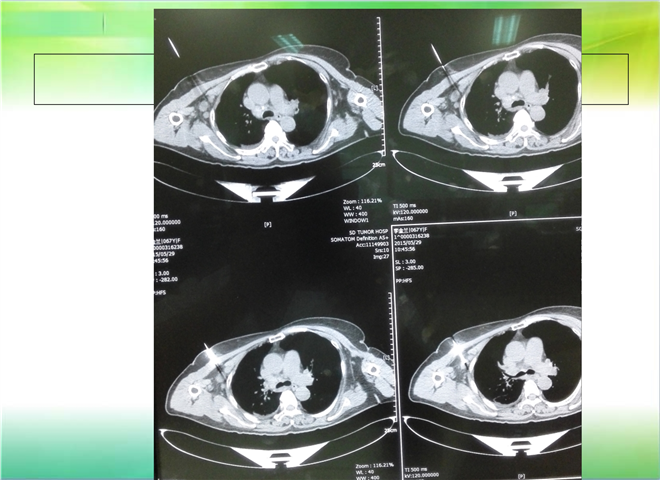

CT引导下穿刺活检术